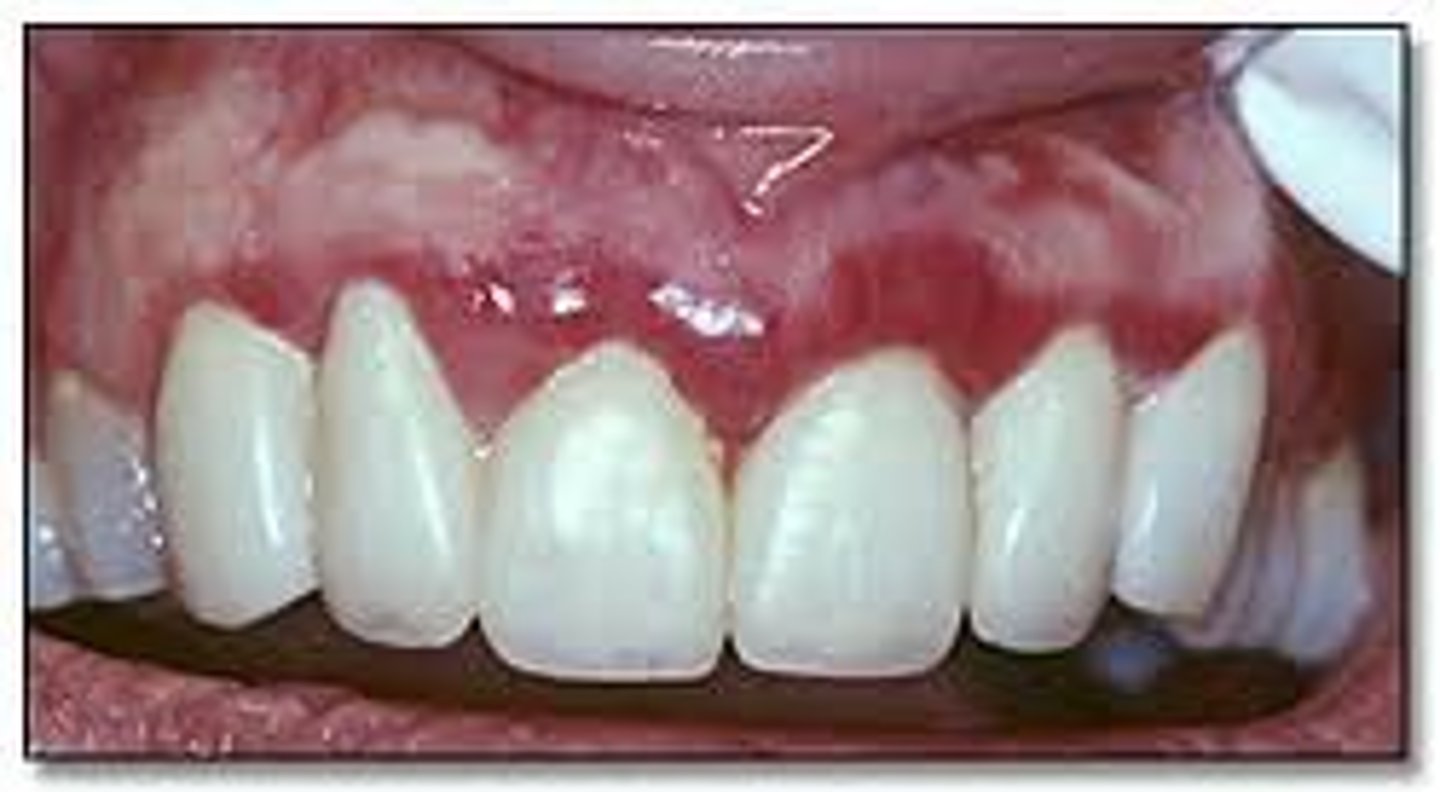

marginal gingivitis

red and swollen

brushing teeth too often

<p>red and swollen</p><p>brushing teeth too often</p>